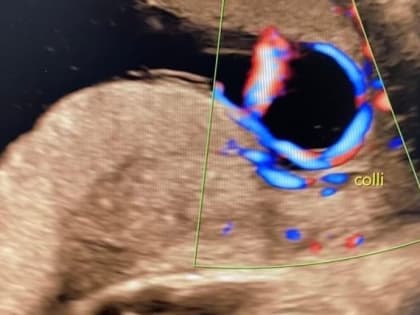

Беременные в Нижнем Новгороде: опасность vasa previa и её диагностика

Специалисты предупреждают о редкой, но серьезной патологии, угрожающей жизни ребенка.